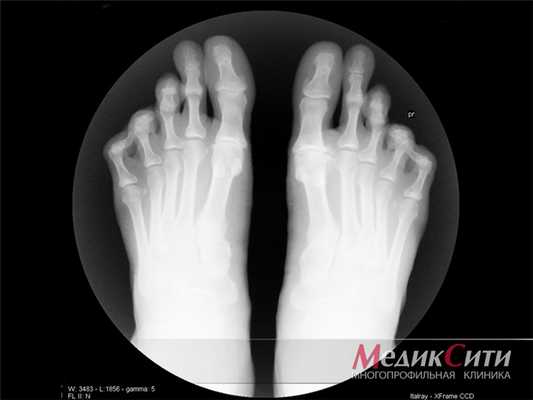

Для постановки диагноза и для проведения дифференциальной диагностики необходимо провести рентгенологическое исследование. Характерным для рентгенологического исследования является:

- наличие крупных кист (тофусов) в субхондральной кости и более глубоко;

- крупные кисты возле сустава и эрозии маленьких размеров на поверхностях сустава, постоянное уплотнение мягких тканей возле сустава, возможно наличие кальцификатов;

- эрозии больших размеров, остеолиз эпифиза, уплотнение тканей, депозиты кальция.

Рентгенография в начале заболевания проводится с целью дифференциальной диагностики с другими артропатиями, специфические же признаки подагры при этом отсутствуют. Только при переходе патологии в хроническую форму на снимках можно увидеть внутрикостные тофусы, краевые эрозии костей.

- Рентгенография. Исследование пораженных суставов определяет развитие тофусов, а также наличие участков с разрушенной суставной и костной тканями;